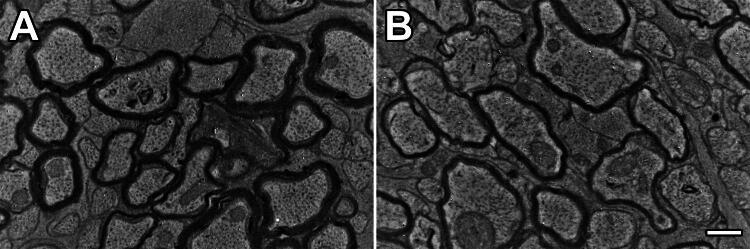

Most studies involving myelin g ratios over the past 120 years assume this metric enumerates differences in myelin thickness (larger g ratio = thinner myelin) with axon or fiber diameter. And, moreover, such changes are directly correlated with internodal function (conduction velocity). However, such assumptions are warranted only in the absence of experimental errors and artifacts (i.e. under theoretical conditions). In reality, g ratios can easily under- or overestimate the rate of change for this relation in excess of 10%, especially for small caliber fibers. Typical analyses of myelin internodes rely on an explicit mathematical model, g ratio=DADF, where DA is axon diameter and DF is fiber diameter (myelin plus axon). Shown recently and herein, this model approximates normal physiological conditions only when the axon-fiber diameter relation is directly proportional, whence it is concordant with the axomyelin unit model. However, in transient or non-steady states (development/aging, disease or myelin plasticity) with linear but not directly proportional relations, g ratios may not accurately describe myelin structure. Acceptance of this counterintuitive assertion is predicated on a detailed understanding of the g ratio - its origins, properties and the biology represented - which has been heretofore unexplored. In light of such g ratio limitations, and toward consistency with experimental data, two more reliable metrics are proposed, the myelin gc ratio and the g' cline. But irrespective which of metric is preferred , the analysis herein shows that the axon-to-fiber diameter ratio under normal physiological conditions is a constant for all fiber diameters.